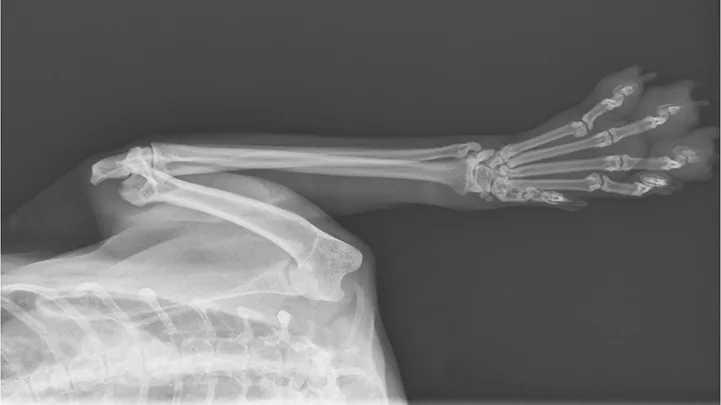

Figure 3

Dorsoventral radiograph revealing lytic lesions associated with distal phalanges consistent with digital metastasis. Image courtesy of Rachel Moon, DVM, DACVR

Feline lung-digit syndrome, a syndrome of multiple digital metastasis, is characterized by disseminated metastasis to the digits and is most commonly associated with bronchial and bronchioloalveolar carcinomas.1,3,5,6 This pattern of metastasis is most frequently diagnosed in older cats (mean age, 12 years; range, 2-20 years5), with no consistently reported breed or sex predilection.1,3-6 The pathogenesis is not well-understood; metastatic lesions are believed to arise via arterial embolization from the tumor.5,6 Tumor metastases are located at atypical sites, most notably the distal phalanges (Figure 3), with the weight-bearing third phalanx of the front feet most frequently affected.6 In addition, multidigit and multilimb involvement are common.6,7

Radiographs may reveal extensive osteolysis of the distal phalanx that may cross the joint space. Thoracic radiographs often show a single primary lung mass, although diffuse nodular disease has also been noted.1 No clinical signs of respiratory distress in affected cats have been reported.6